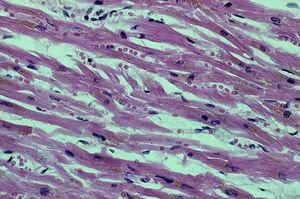

Músculo cardíaco visto al microscopio.

La agrupación de varias células que realizan la misma función forma un tejido. Por ejemplo, el tejido muscular está formado por un tipo especial de células, llamadas fibras muscular ...